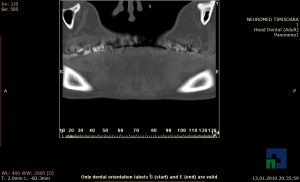

În cazul traumatismelor cranio-cerebrale:

- Diagnosticul edemului cerebral, a contuziei cerebrale, a leziunilor axonale difuze edematoase/hemoragice, a dilacerării cerebrale, a hematomului intraparenchimatos posttraumatic, a hematoamelor subdurale/extradurale (acute, subacute, cronice), a hemoragiei intraventriculare, a hemoragiei subarahnoidiene

- Diagnosticul traumatismelor de bază de craniu

- Diagnosticul fracturilor: